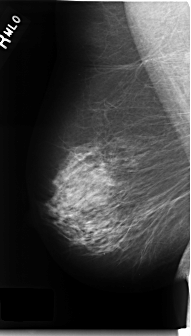

C_0228_1.RIGHT_MLO

RIGHT_MLO LINES 4704 PIXELS_PER_LINE 2672 BITS_PER_PIXEL 12 RESOLUTION 50 NON_OVERLAY